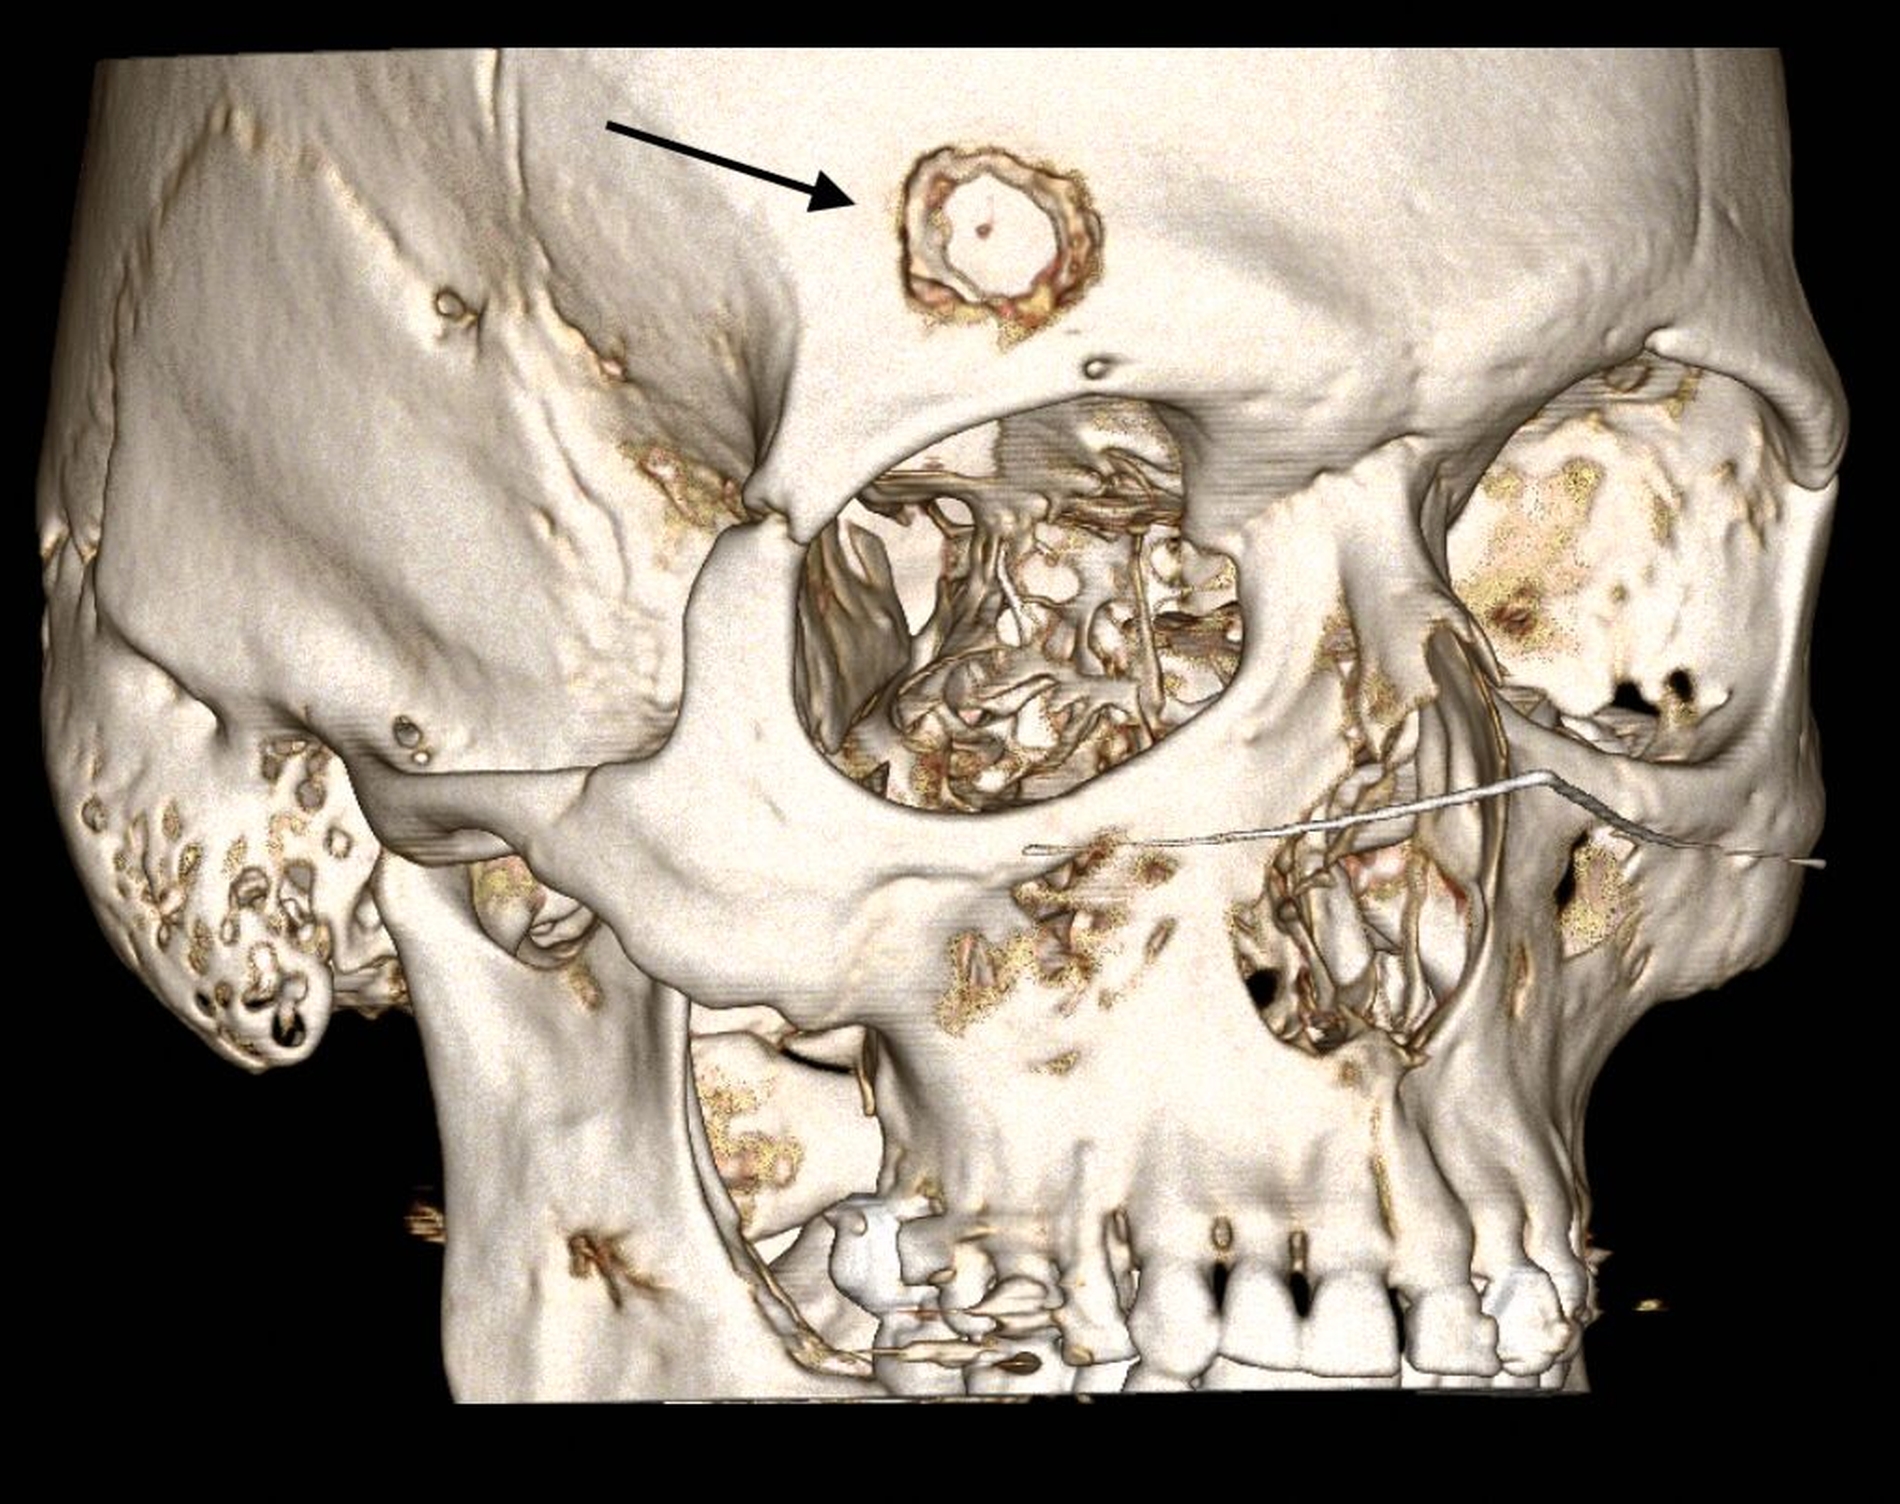

Ein 48-jähriger Mann stellte sich in der mund-, kiefer-, gesichtschirurgischen Ambulanz vor aufgrund einer seit anderthalb Jahren größenprogredienten, schmerzhaften Schwellung im Bereich der rechtsseitigen Stirn, wo er im Rahmen seiner beruflichen Tätigkeit ein Anpralltrauma mit einem metallischen Gegenstand erlitten hatte (Abbildung 1). Der ansonsten gesunde Patient berichtete von dauerhaften mäßigen Ruheschmerzen, die bereits bei leichter Berührung der Schwellung stark zunahmen.

In der klinischen Untersuchung zeigte sich eine harte, unverschiebliche und gut begrenzte Raumforderung. Die sonografische Untersuchung erbrachte keinen wegweisenden Befund, so dass eine Computertomografie (CT) des Mittelgesichts mit Kontrastmittel durchgeführt wurde. Hier konnte eine supraorbital im Os frontale gelegene, glatt begrenzte Raumforderung mit feingranulierter Verkalkung und einer Ausdehnung von circa 2 cm x 2 cm x 1 cm dargestellt werden.

Diese überschritt nach ventral bereits die Kortikalis und wurde nach dorsal nur noch durch eine dünne Knochenlamelle von den Meningen abgegrenzt. Insgesamt passte der Befund CT-morphologisch zu einem Kalottenhämangiom, differenzialdiagnostisch war auch ein Eosinophiles Granulom möglich (Abbildungen 2 bis 4).